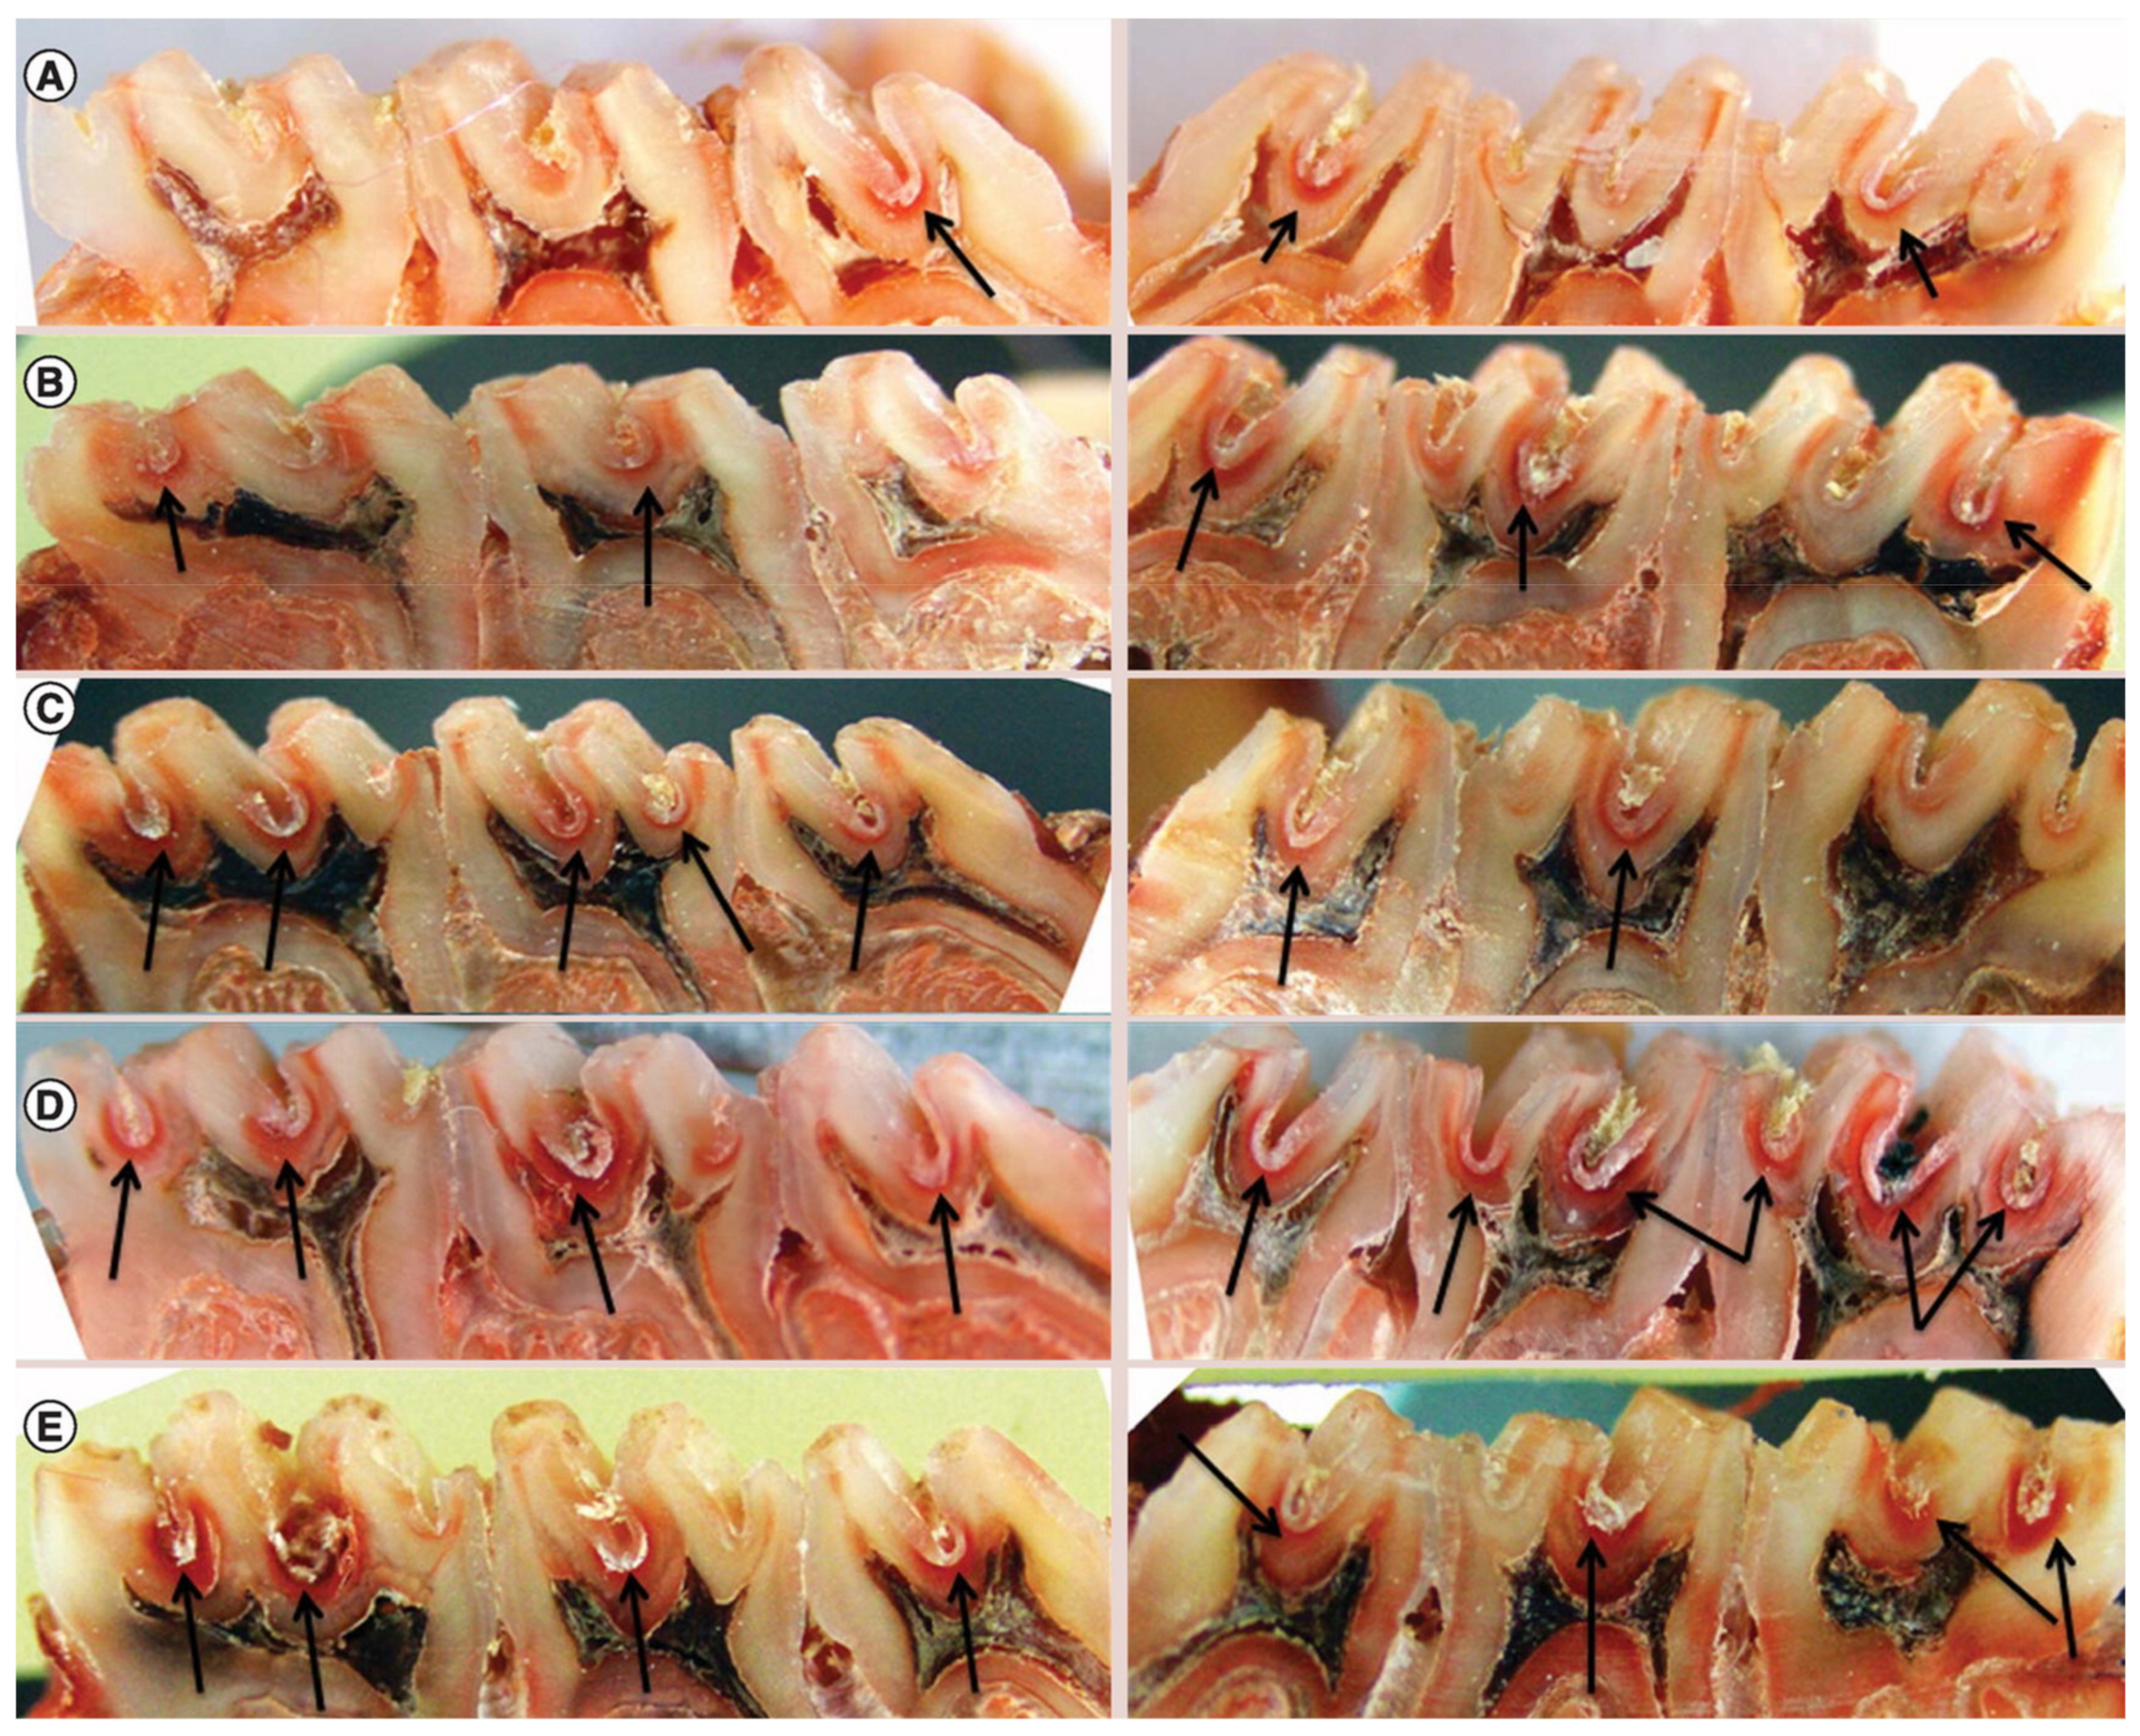

5.4. Ex Vivo Models

5.5. In Vivo Models